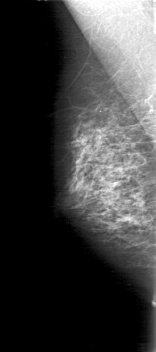

D_4038_1.LEFT_MLO

LEFT_CC LINES 5041 PIXELS_PER_LINE 2056 BITS_PER_PIXEL 12 RESOLUTION 43.5 OVERLAY

LEFT_MLO LINES 5026 PIXELS_PER_LINE 2476 BITS_PER_PIXEL 12 RESOLUTION 43.5 OVERLAY